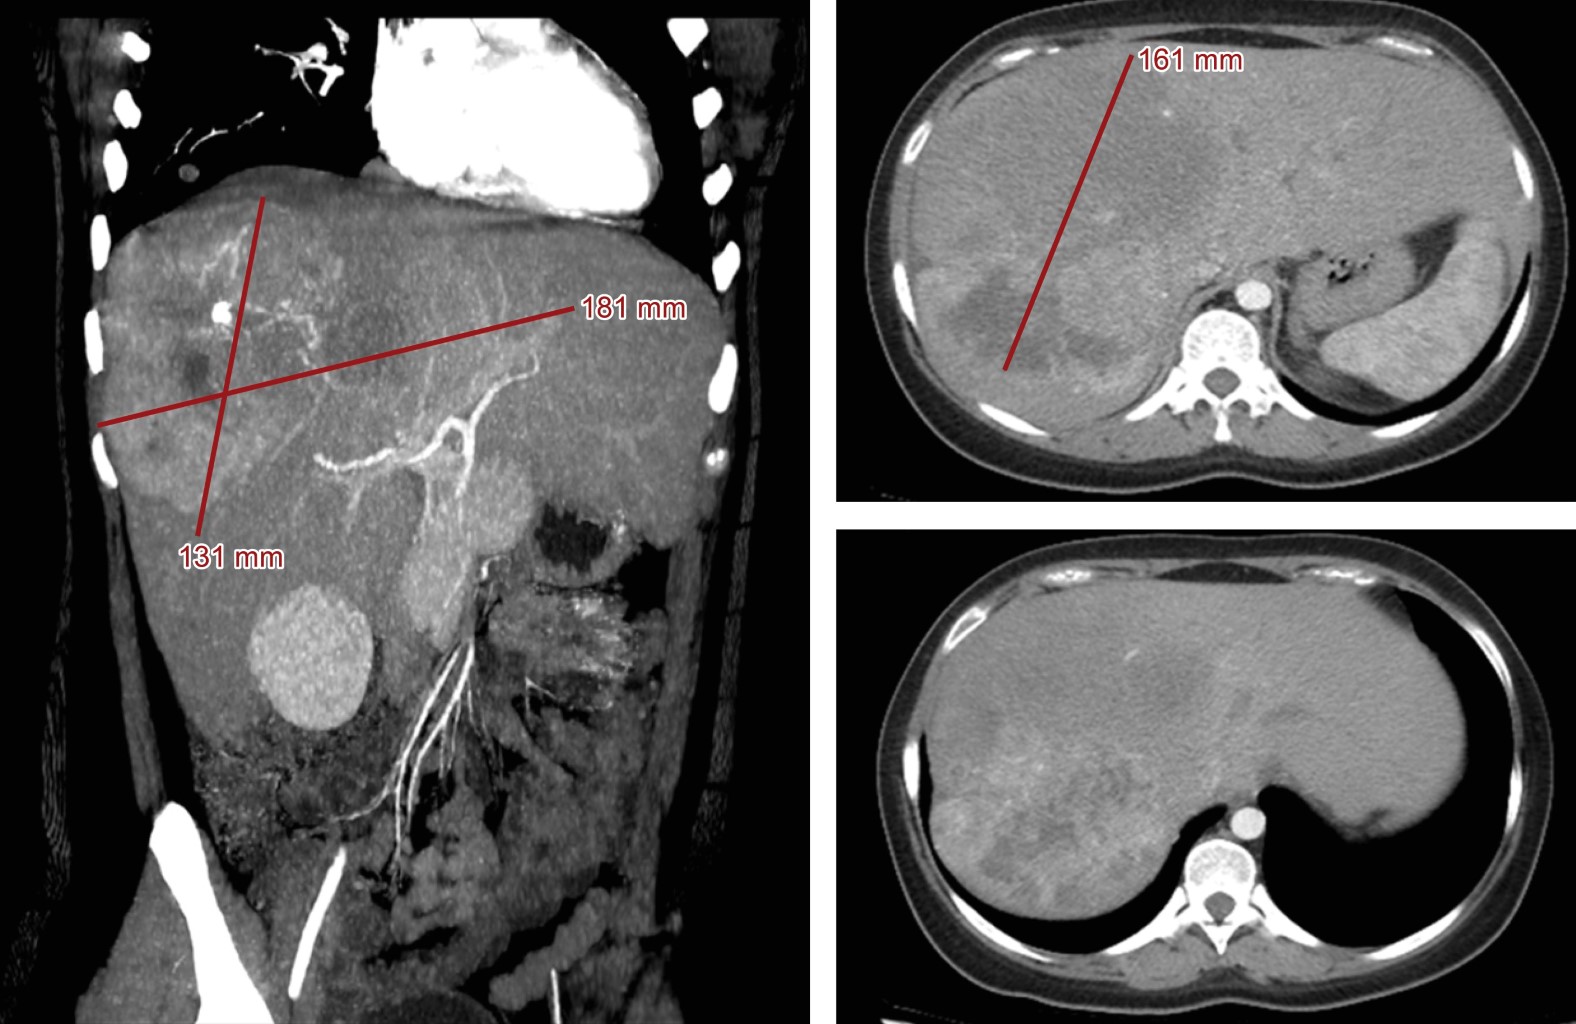

Introduction: fibrolamellar hepatocellular carcinoma (FLC) is a rare form of hepatocellular carcinoma affecting young patients. We present a case of unresectable FLC treated with transarterial chemoembolization and a combination of atezolizumab and bevacizumab. Case description: a 20-year-old woman with abdominal pain, nausea, and vomiting was diagnosed with well-differentiated FLC. A dual therapy regimen was implemented, achieving a 26.7% reduction in lesion size, maintained for 18.13 months. The overall survival was 22.23 months. Conclusion: FLC differs from conventional hepatocellular carcinoma and presents therapeutic challenges. The combination of chemoembolization and immunotherapy shows promising potential. This case adds valuable information about FLC in our country.

Figure 2